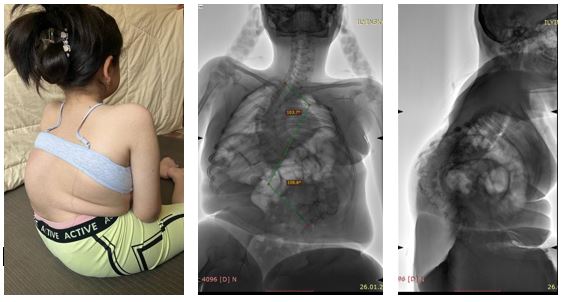

Недавно в один день двумя хирургическими бригадами в соседних операционных были прооперированы родные сёстры — 12 и 8 лет — с тяжёлым генетическим заболеванием, спинальной мышечной атрофией.

При подобных заболеваниях деформация позвоночника прогрессирует значительно быстрее и протекает тяжелее, чем при обычном идиопатическом подростковом сколиозе. Искривление влияет не только на внешний вид, но и на:

• способность удерживать тело в вертикальном положении (в первую очередь — возможность сидеть);

• работу сердечно-сосудистой и дыхательной систем;

• переносимость реабилитационных мероприятий;

• качество жизни ребенка и ухода за ним.